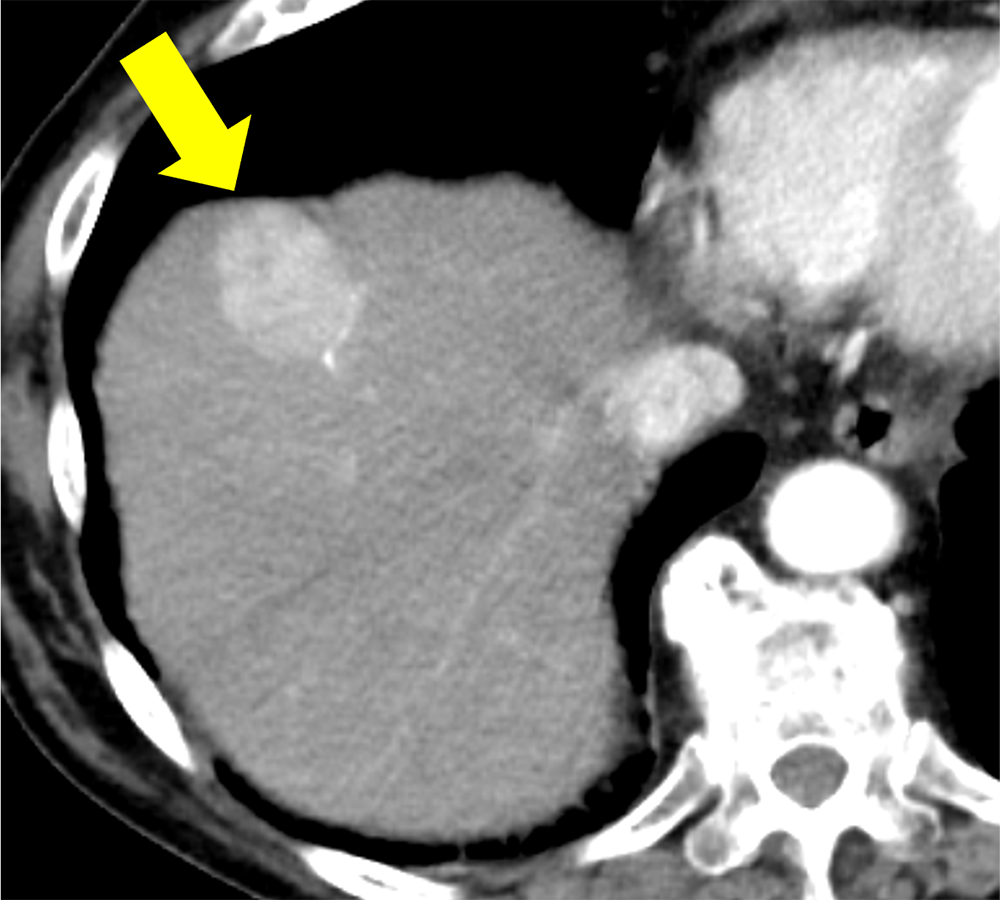

アルコール性肝障害の既往あり。人間ドックの腹部超音波検査で肝腫瘤を指摘され、撮像された造影CTで肝S8の多血化肝細胞癌と診断とされた。単発の病変であり、腹腔鏡下肝S8亜区域切除術が施行された。術後3日目に腹壁瘢痕ヘルニアによる小腸閉塞があり、イレウス解除および腹壁瘢痕ヘルニア修復術が施行された。以降は腫瘍の再発なく経過観察を継続している。

CT技術や撮像プロトコル設定について

今回の造影CTでは造影剤注入を一定速度で注入するのではなく、注入速度を連続的に減少させながら注入する可変注入を用いている。造影剤の総量や注入時間は変化させず、注入速度のみを変化させるため、通常注入と比べて注入開始時の速度は上昇し、終了時の速度は低下する。つまり注入の前半により多くの造影剤を注入し、後半に注入される造影剤は減少する。通常注入を行った場合、動脈相の撮像時点では注入された造影剤の一部は病変には到達しておらず、多血化の評価に活用されている造影剤量は想定よりも少ない可能性があるが、可変注入で注入前半に多くの造影剤を注入することで、より多くの造影剤を多血化の評価に活用することができる。また従来の注入法と比べて可変注入法では大動脈の造影効果のピークが前倒し、ピークのCT値も上昇する。これらにより多血化肝細胞癌の造影効果が上昇し、腫瘍と背景肝のコントラストが上昇する。また従来法では早期動脈相では腫瘍の造影効果は通常得られないが、可変注入法では早期動脈相から腫瘍の造影効果が得られ、まだCT値が上昇していない背景肝とのコントラストが良好となり、多血化肝細胞癌の検出能を向上させる可能性がある。